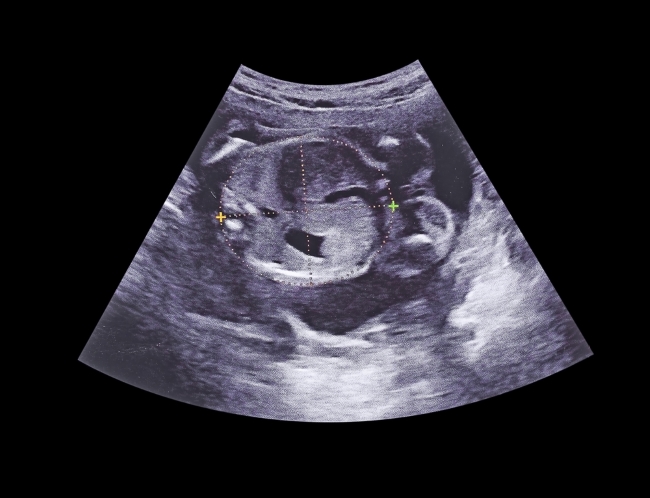

Wajah janin pada usia 5 bulan sudah mulai terlihat seperti bayi. Mata yang sebelumnya berada di samping kepala kini berpindah ke bagian depan, hidung dan telinga mulai menonjol, serta bibir dan dagu terbentuk lebih nyata. Selain itu, jari-jari tangan dan kaki sudah terpisah dengan baik, bahkan kuku-kuku mungil mulai tumbuh. Perubahan ini bisa terlihat jelas saat dilakukan pemeriksaan USG.